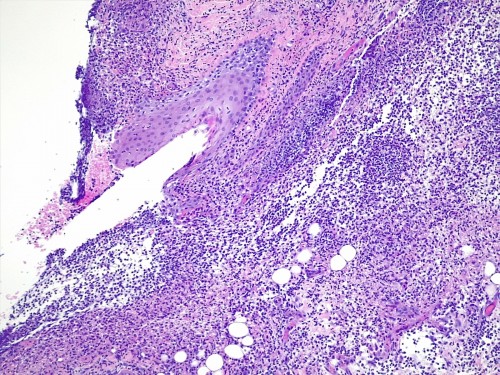

– les biopsies cutanées (LAPVSO) concluent à de sévères lésions de dermohypodermite neutrophilique avec furonculose et lésions hypodermiques ponctuelles de vascularite leucocytoclasique (Photos 4 à 9)

Examen histopathologique montrant un épiderme intact ou sévèrement ulcéré. Dans le derme, on observe un œdème superficiel ainsi que de multiples foyers inflammatoires non encapsulés, souvent à point de départ folliculaire ou périfolliculaire, pouvant fusionner, rompre les follicules pileux et s’étendre dans l’ensemble du derme voire gagner l’hypoderme. Ces foyers sont caractérisés par l’accumulation de granulocytes neutrophiles qui semblent altérés et qui dissèquent les fibres de collagène autour du follicule pileux ainsi que la paroi folliculaire et la lumière folliculaire. De nombreuses plages inflammatoires contiennent des tiges pilaires nues. L’infiltrat peut s’étendre dans l’hypoderme, mais ce dernier est surtout caractérisé par un épaississement des septa conjonctifs interlobulaires du tissu adipeux avec œdème, accumulation d’un matériel fibrinoïde, dilatation vasculaires des vaisseaux lymphatiques et des structures vasculaires de petit calibre, les vaisseaux lymphatiques étant encombrés d’un matériel inflammatoire fibrino-leucocytaire. Il peut exister des images focales de vascularite leucocytoclasique au sein de l’hypoderme.